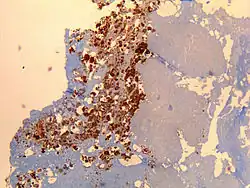

| Immunohistochemical detection of C. burnetii in resected cardiac valve of a 60-year-old man with Q fever endocarditis, Cayenne, French Guiana: Monoclonal antibodies against C. burnetii and hematoxylin were used for staining; original magnification is ×50. | |